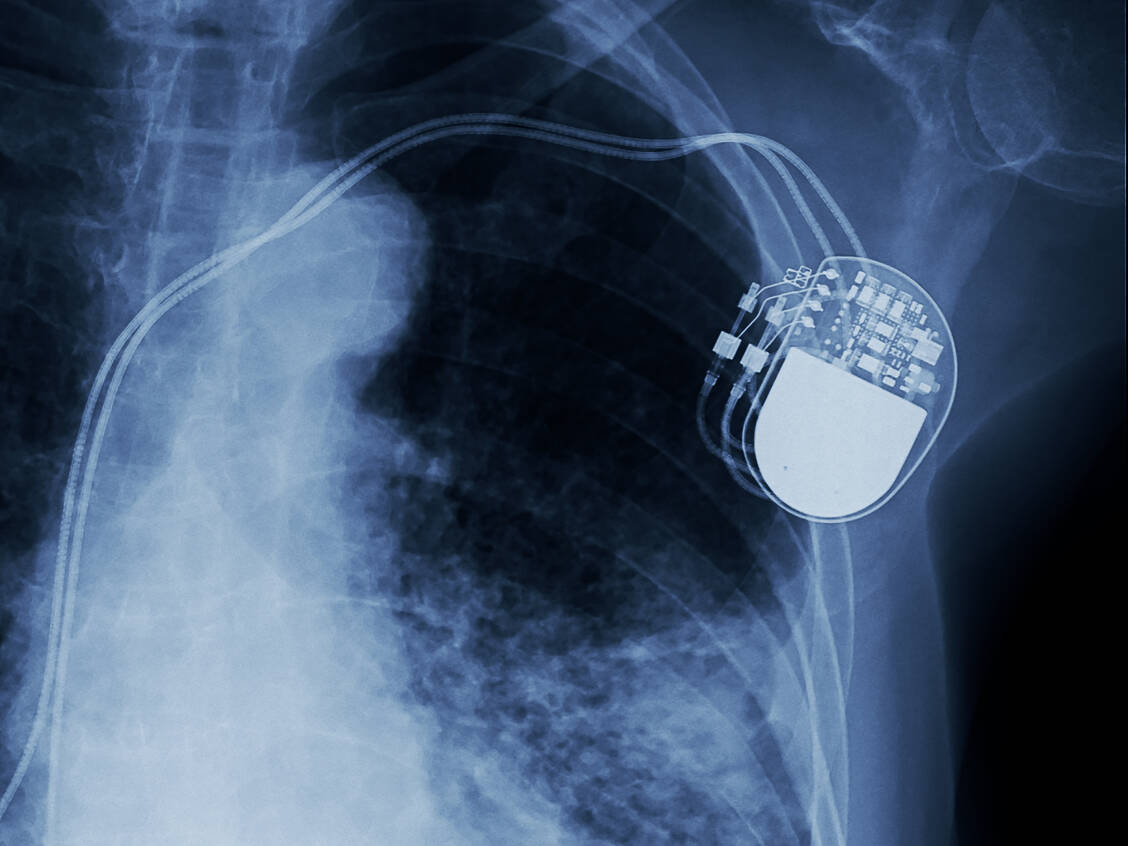

Spahn will die Risikobewertung und Überwachung von Produkten wie künstliche Knie- oder Hüftgelenke, Herzschrittmacher und chirurgisches Besteck auf Bundesebene zentralisieren. Bisher ist der Bund für die Risikoeinschätzung zuständig, die Länder für die Überwachung. Konkret sollen künftig das Bundesinstitut für Arzneimittel und Medizinprodukte (BfArM) und das Paul-Ehrlich-Institut (PEI) für die Aufsicht und Kontrolle zuständig sein. Im Frühjahr hatte Spahn zudem angekündigt, Implantate zentral registrieren zu lassen, um mehr Qualität und Sicherheit für die Patienten zu erreichen.